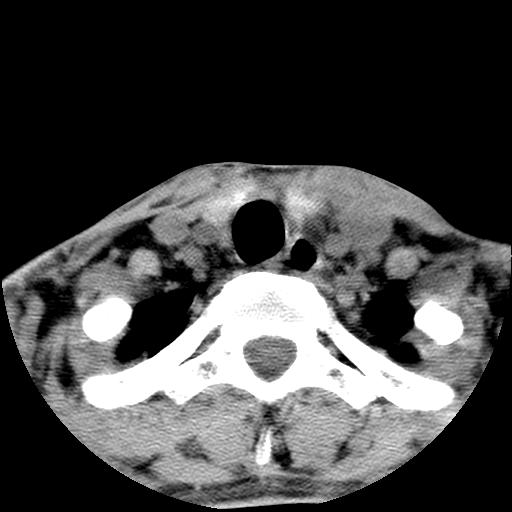

标题: CT15118:f-27y,左颈部肿一个月,无发热、无压痛 [打印本页]

标题: CT15118:f-27y,左颈部肿一个月,无发热、无压痛

1、甲状腺左叶病变:腺瘤?结节性增生?其他?

2、上极周围间隙病变。

3、2者关系?

左侧甲状腺肿大,密度不均.同侧甲状软骨似有破坏(建议传骨窗).左侧颈静脉增粗,各组织之间分界不清,有多个肿大淋巴结.甲状腺肿并感染?临床症状不符.淋巴结核?请结合其他检查.